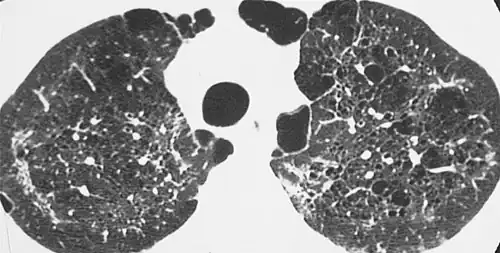

The diagnosis can be confirmed by the characteristic appearance of the chest X-ray and an arterial oxygen level (PaO2) that is strikingly lower than would be expected from symptoms. Gallium 67 scans are also useful in the diagnosis. They are abnormal in about 90% of cases and are often positive before the chest X-ray becomes abnormal. Chest X-ray typically shows widespread pulmonary infiltrates. CT scan may show pulmonary cysts (not to be confused with the cyst-forms of the pathogen).

High-resolution computed tomography (HRCT) showing ground-glass attenuation with a geographic or mosaic distribution.[7] -

HRCT of cysts of pneumocystis pneumonia. These are usually multiple and bilateral, but range in size, shape and distribution.[7]